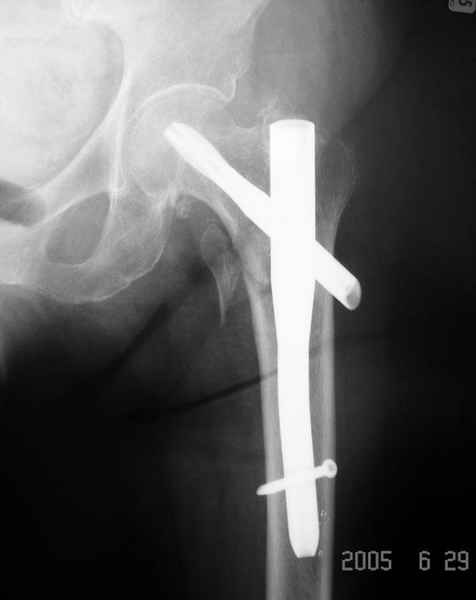

Другие случаи: применение Synthes TTFN (trochanteric titanium femoral nail) и Blade Plate (угловая пластина), так что много различных вариантов фиксации подобных переломов.